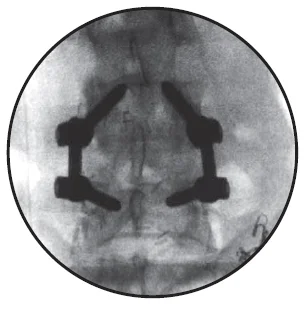

The nerve roots are then moved to one side and the disc material removed from the front (anterior) of the spine. A bone graft is then inserted into the disc space. The bone graft material acts as a bridge, or scaffold, on which new bone can grow. Screws and rods are inserted to stabilize the spine while the treated area heals and fusion occurs, and the ultimate goal of the procedure is to restore spinal stability.